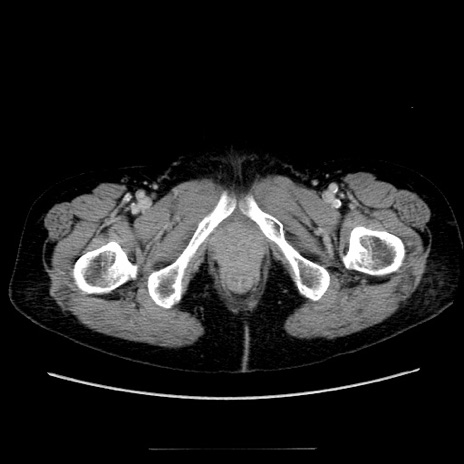

症例5(横断像)

【症例】70歳代女性

【主訴】お腹が張る

【現病歴】1週間くらい前から腹部膨満の自覚あり。昨日夜から増悪したため、本日救急外来受診。

【身体所見】意識清明、BT 36.5℃、BP 165/106mmHg、HR 80bpm、SpO2 98%、腹部:膨満、軟、自発痛・圧痛なし、触診にて不快感あり、腸蠕動音:減弱

【データ】WBC 12600、CRP 1.04